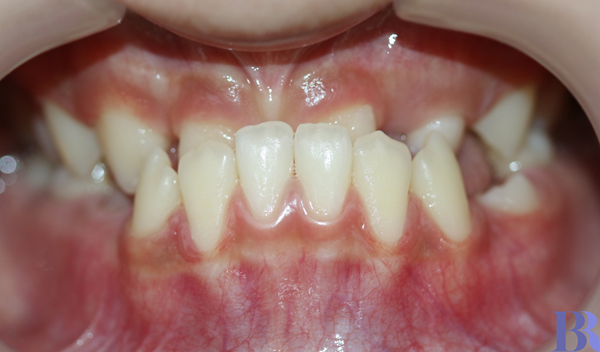

아랫니가 심하게 거꾸로 물림(반대교합)

<내원 이유>

"치아가 거꾸로 물려서

앞니로 끊어 먹기 힘들고

위에 앞니 두 개도 없어요."

환자 연령 : 12세

치료기간 : 3년

치료방법 : 비발치

치료장치 : 클리피씨